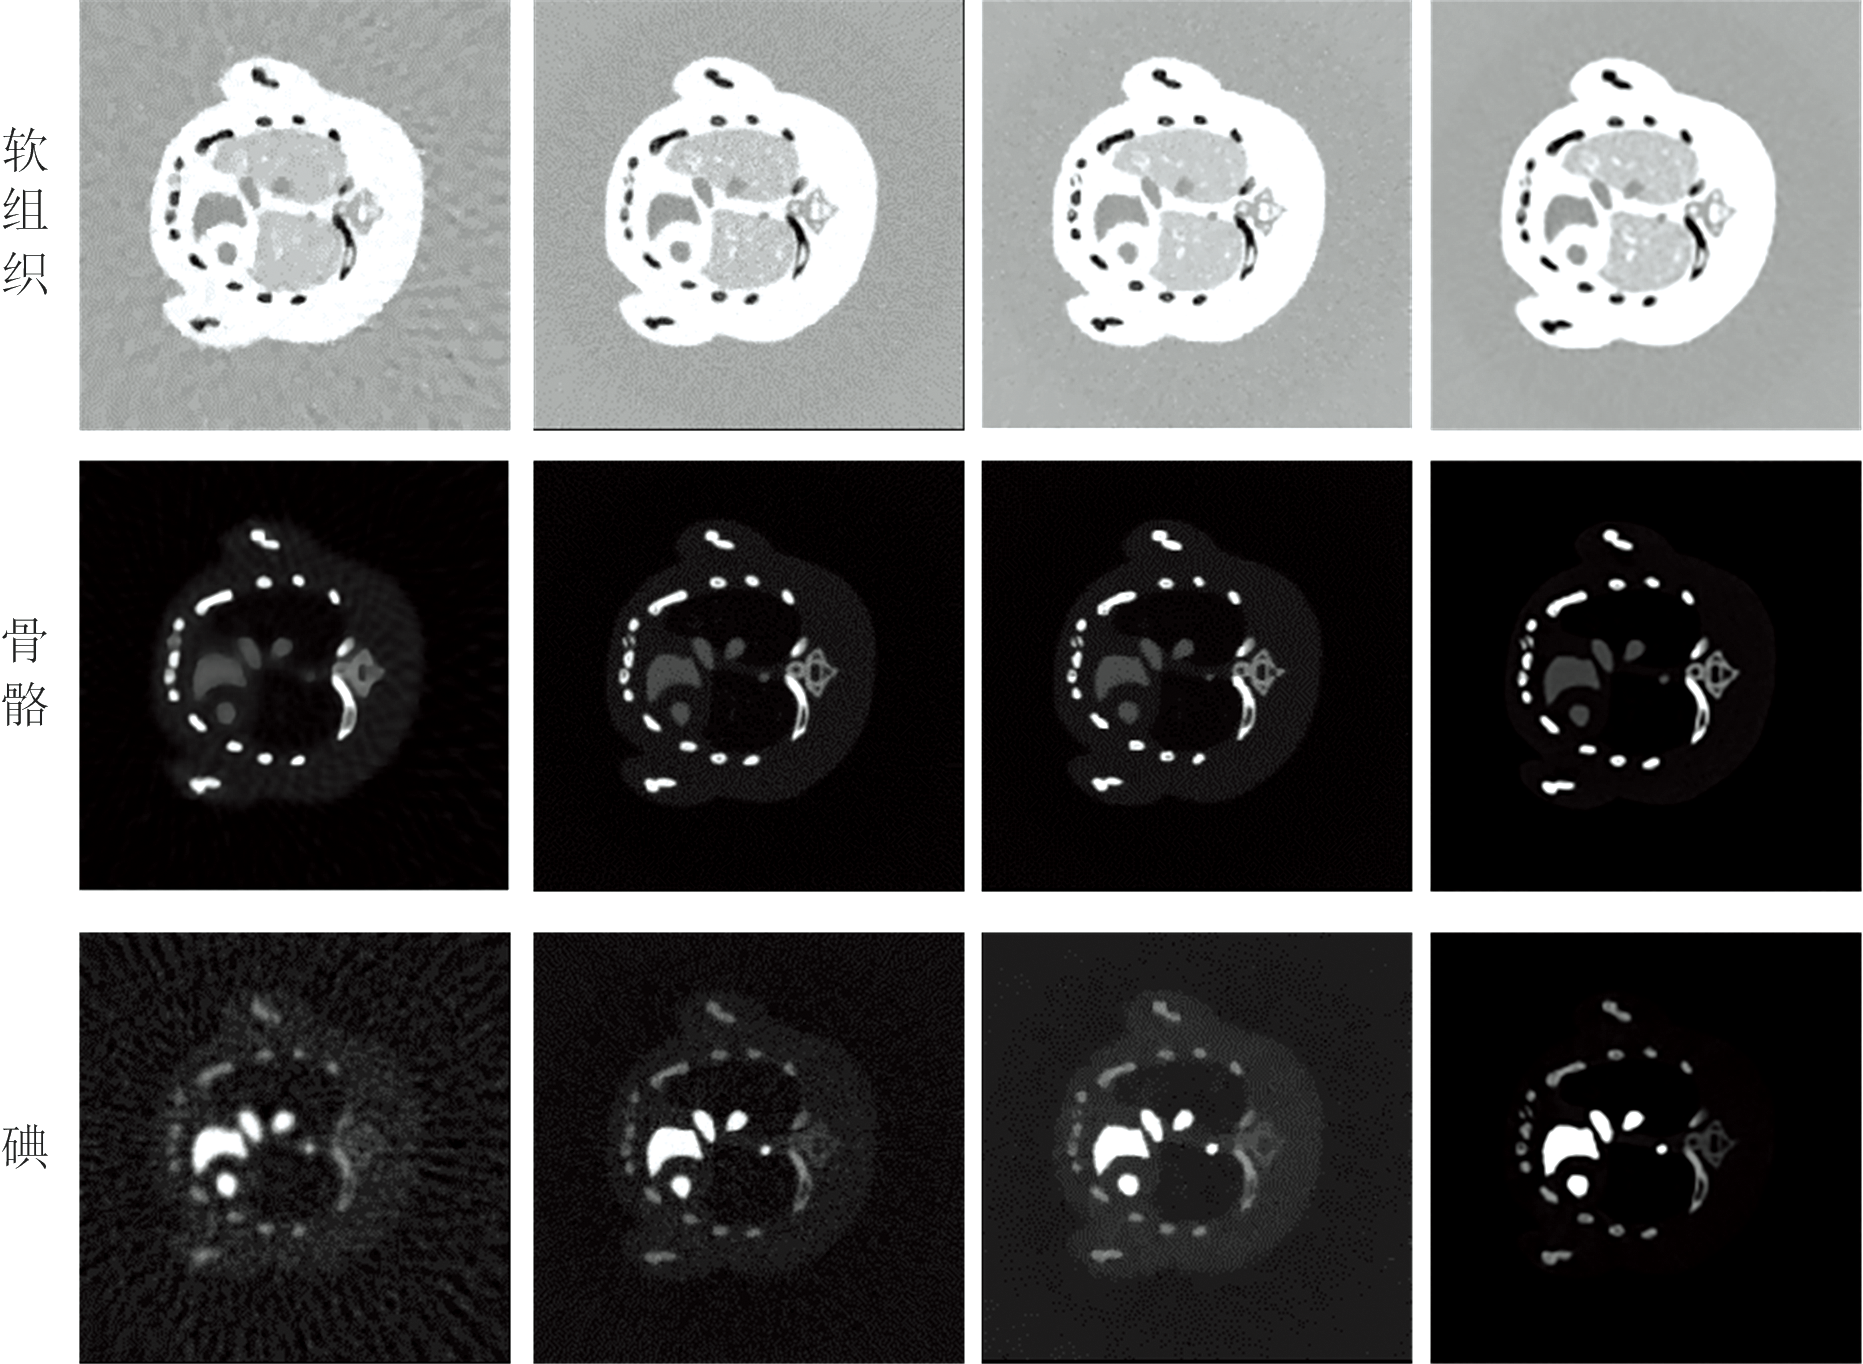

图4(a— d)是分别在不同步骤上加入正则化获得的四种基材料图像结果。 从左到右依次为PD-MR方法、 TV4-MR方法、 PD-TV4方法作为对比方法和本文提出的D-TV4方法。 从图4中可以看出, 在PD-MR结果中软组织和骨骼图像受到严重的噪声污染, 其细微结构和特征被噪声淹没; 钆和碘图像重建过程中还产生了条纹伪影的干扰, 且碘中存在少量骨物质的串扰, 分解准确性降低。 与PD-MR方法相比, TV4-MR方法和PD-TV4方法能够提供更好的材料图像质量。 在TV4-MR结果中, 分解中的噪声得到了部分抑制, 但在重建时图像特征周围伪影严重, 这是由于SART重建的图像引起伪影, 最终的分解结果受到影响。 PD-TV4结果中, 钆和碘图像的伪影被有效去除, 但分解步骤受到严重噪声的干扰, 骨骼图像的边缘结构未能准确分出。 然而, D-TV4方法可以进一步提高材料成分的准确性, 四种物质的分解结果都得到很好的噪声伪影抑制效果且物质边缘细节结构清晰。 由于D-TV4继承了PD-TV4和TV4-MR的优点, 它在材料分解和重建中可以进一步提高材料精度, 进而获得高质量的基材料图像。

在5× 105光子数下进行小鼠胸腔仿真实验, 投影域分解步骤采用LS算法、 SR-TF算法作为比较算法, 对所提出算法的分解效能加以验证。 投影分解结果如图5所示, 分解的基材料投影重建结果如图6所示。 由图6(a— d)可知, 小鼠胸腔仿真实验的各方法结果与模体仿真实验类似。 PD-MR分解的图像受到强噪声和伪影的污染。 PD-TV4结果中软组织和碘图像存在更多的噪声干扰。 TV4-MR获得了较好的分解结果, 但对额外产生的伪影没有明显见效。 而使用本文方法分解的图像, 具有更好的结果。 尤其在碘造影剂方面, 可以看出碘图像在清晰度和边缘锐利度方面表现最优, 其噪声水平和伪影数量显著低于对比方法的结果。 此外, 还消除了

前三种对比方法中残留的软组织结构。 因此本文所提出的D-TV4 方法在投影域材料分解中可以获得高精度的碘图像。 同样计算PSNR和RMSE来评估四种方法对模拟小鼠胸腔的分解性能, 结果如表3所示。 由表3可知, 本文提出的D-TV4 方法的各基材料PSNR值更高且对应的RMSE值也最小, 图像质量更好。

通过定性与定量的分析, 在投影域基材料分解上, 相较于PD-MR、 TV4-MR和PD-TV4算法, 本文提出的D-TV4算法在材料分解性能中表现更好, 不仅能实现清晰的材料分离与锐利的边缘保持, 还能减小受其他物质串扰的影响。 在微小结构方面相对保留了一些细节特征, 有效抑制了噪声和伪影, 使图像更加清晰, 分解质量更高。

图7展示了4种算法下分解的临床前真实小鼠基材料重建图像, 可以看出, 每个算法分解的效果与以上仿真实验分解的效果基本相同。 前三种算法的分解结果都有较大噪声和伪影的干扰, 物质边缘结构模糊。 而D-TV4算法分解的软组织图像结构更加明显, 且噪声和伪影更少。 骨骼图像对比黄框中骨物质的边缘结构, 可以看出本文算法分解的骨更清晰, 细节更加突出。